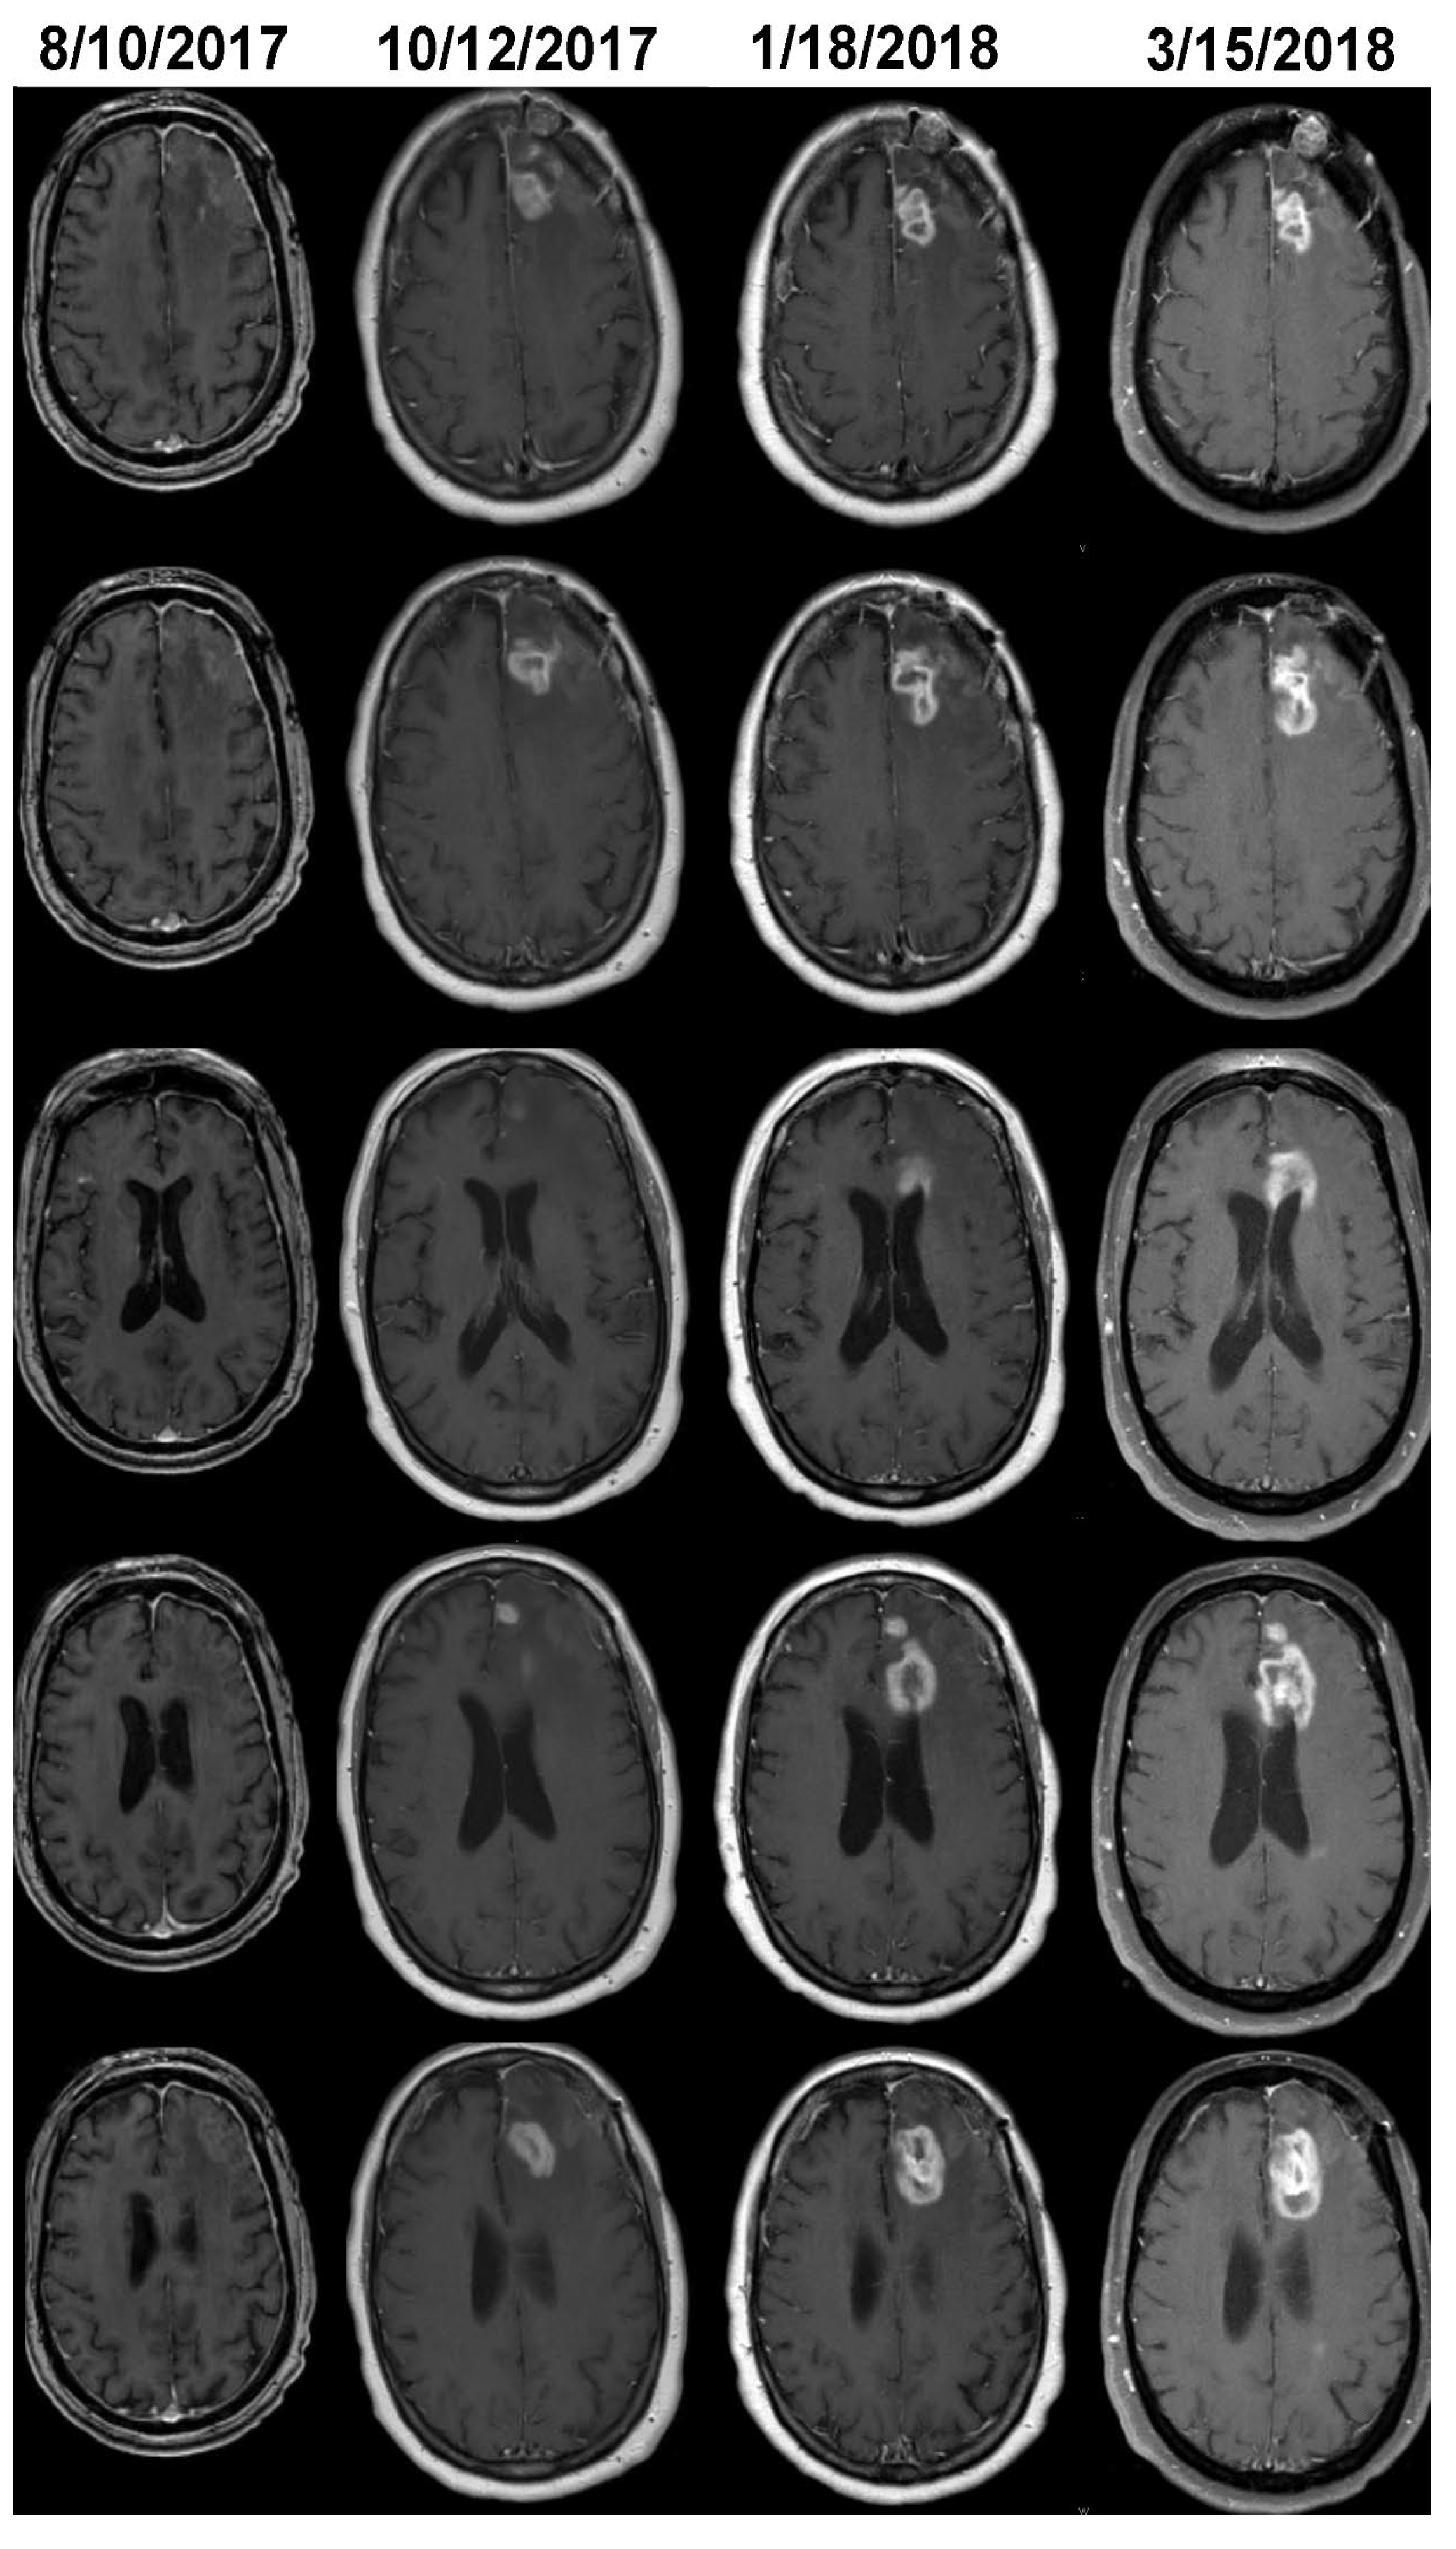

The MRI of case 2 on 8/10/2017 reveals a surgical bed with linear enhancement along its margin (Figure 3). The neuro-oncologist diagnosed progression on 3/15/2017 (Figure 3). Volumetric analysis detected growth on 10/12/2017 (Figure 3); additional GBM growth can be seen on 1/18/2018; the treating neuro-oncologist did not change the clinical management until 3/15/2018. In case 4, tumor volume was stable for 6 months after the initial growth detected by the change-of-point method; this appears to be secondary to either an initial period of PsPD followed by real growth or nonlinear growth (Figure 1).

Figure 3. The T1c images of Case 2 (see Table 1 and Figure 1) shown before (8/10/2017) and at the time of detection of growth by volumetric analysis on 10/12/2017. The neuro-oncologist informed the family of progression and initiated new clinical actions on 3/15/2018. Additional tumor growth can be seen on the MRI performed on 1/18/2018.